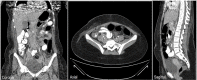

Although Meckel's diverticulum (MD) is a relatively common asymptomatic gastrointestinal anomaly, an inverted MD is a rare entity that is challenging to diagnose prior to surgery and presents usually in the pediatric population with bleeding, anemia and abdominal pain. The most frequent adult presentation in non-inverted MD is intestinal obstruction, whereas bleeding and anemia are the most typical presenting complaints in inverted MD. Here, we report our experience with an adult female patient, who presented with 5 days duration of abdominal pain, nausea and vomiting. Imaging revealed signs of small bowel obstruction with bowel wall thickening in the terminal ileum and a double target appearance. This case describes a rare cause of adult intestinal intussusception because of inverted MD, which was successfully managed with surgery. The final pathology report confirms the diagnosis.